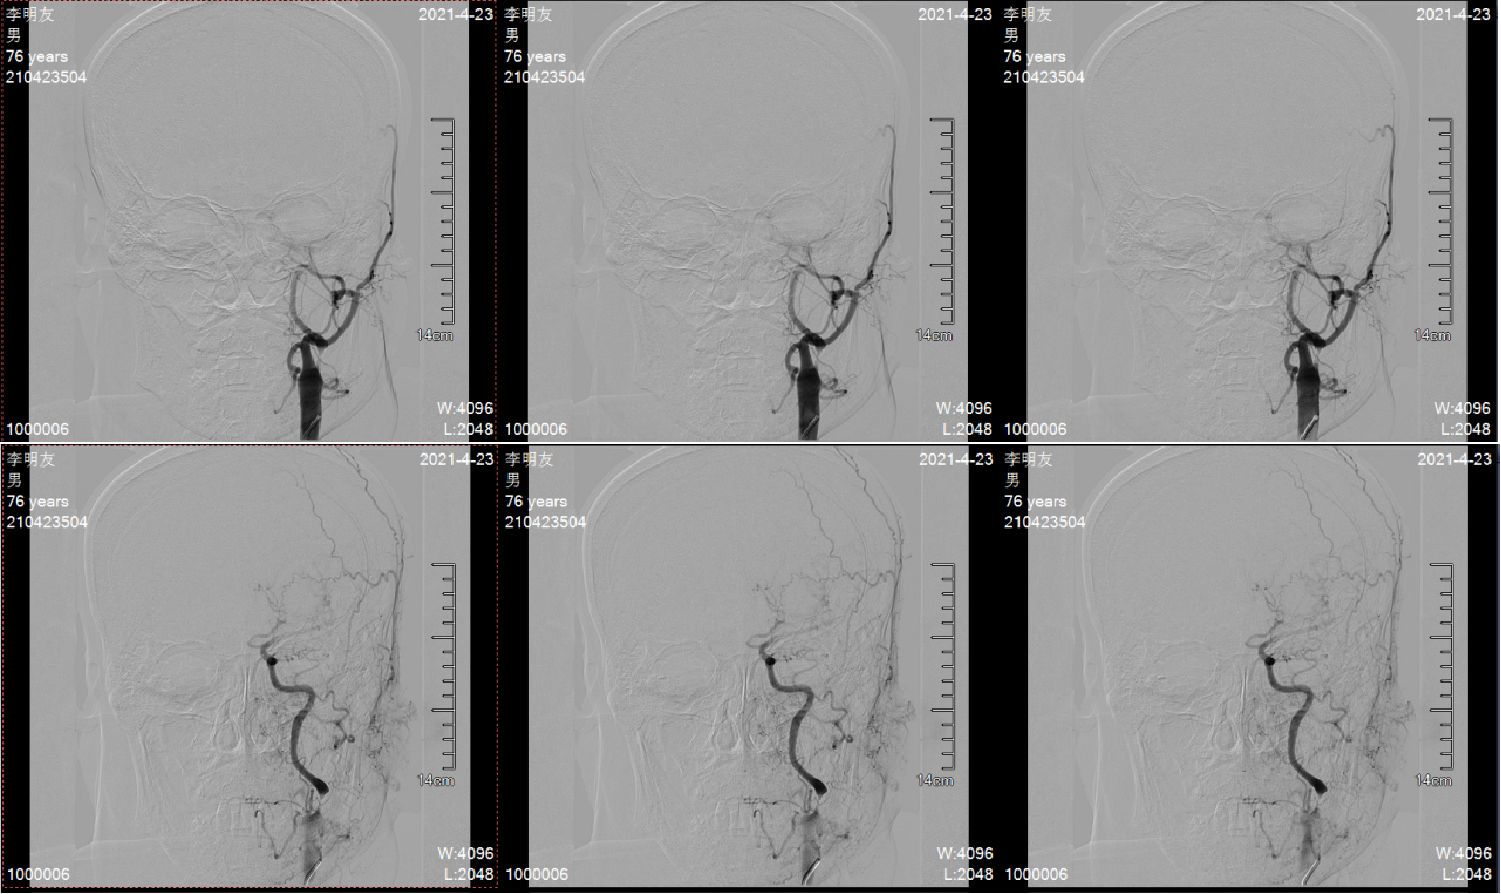

造影显示左侧颈内动脉重度狭窄,远端血流缓慢;狭窄部位在颈2、3椎体水平